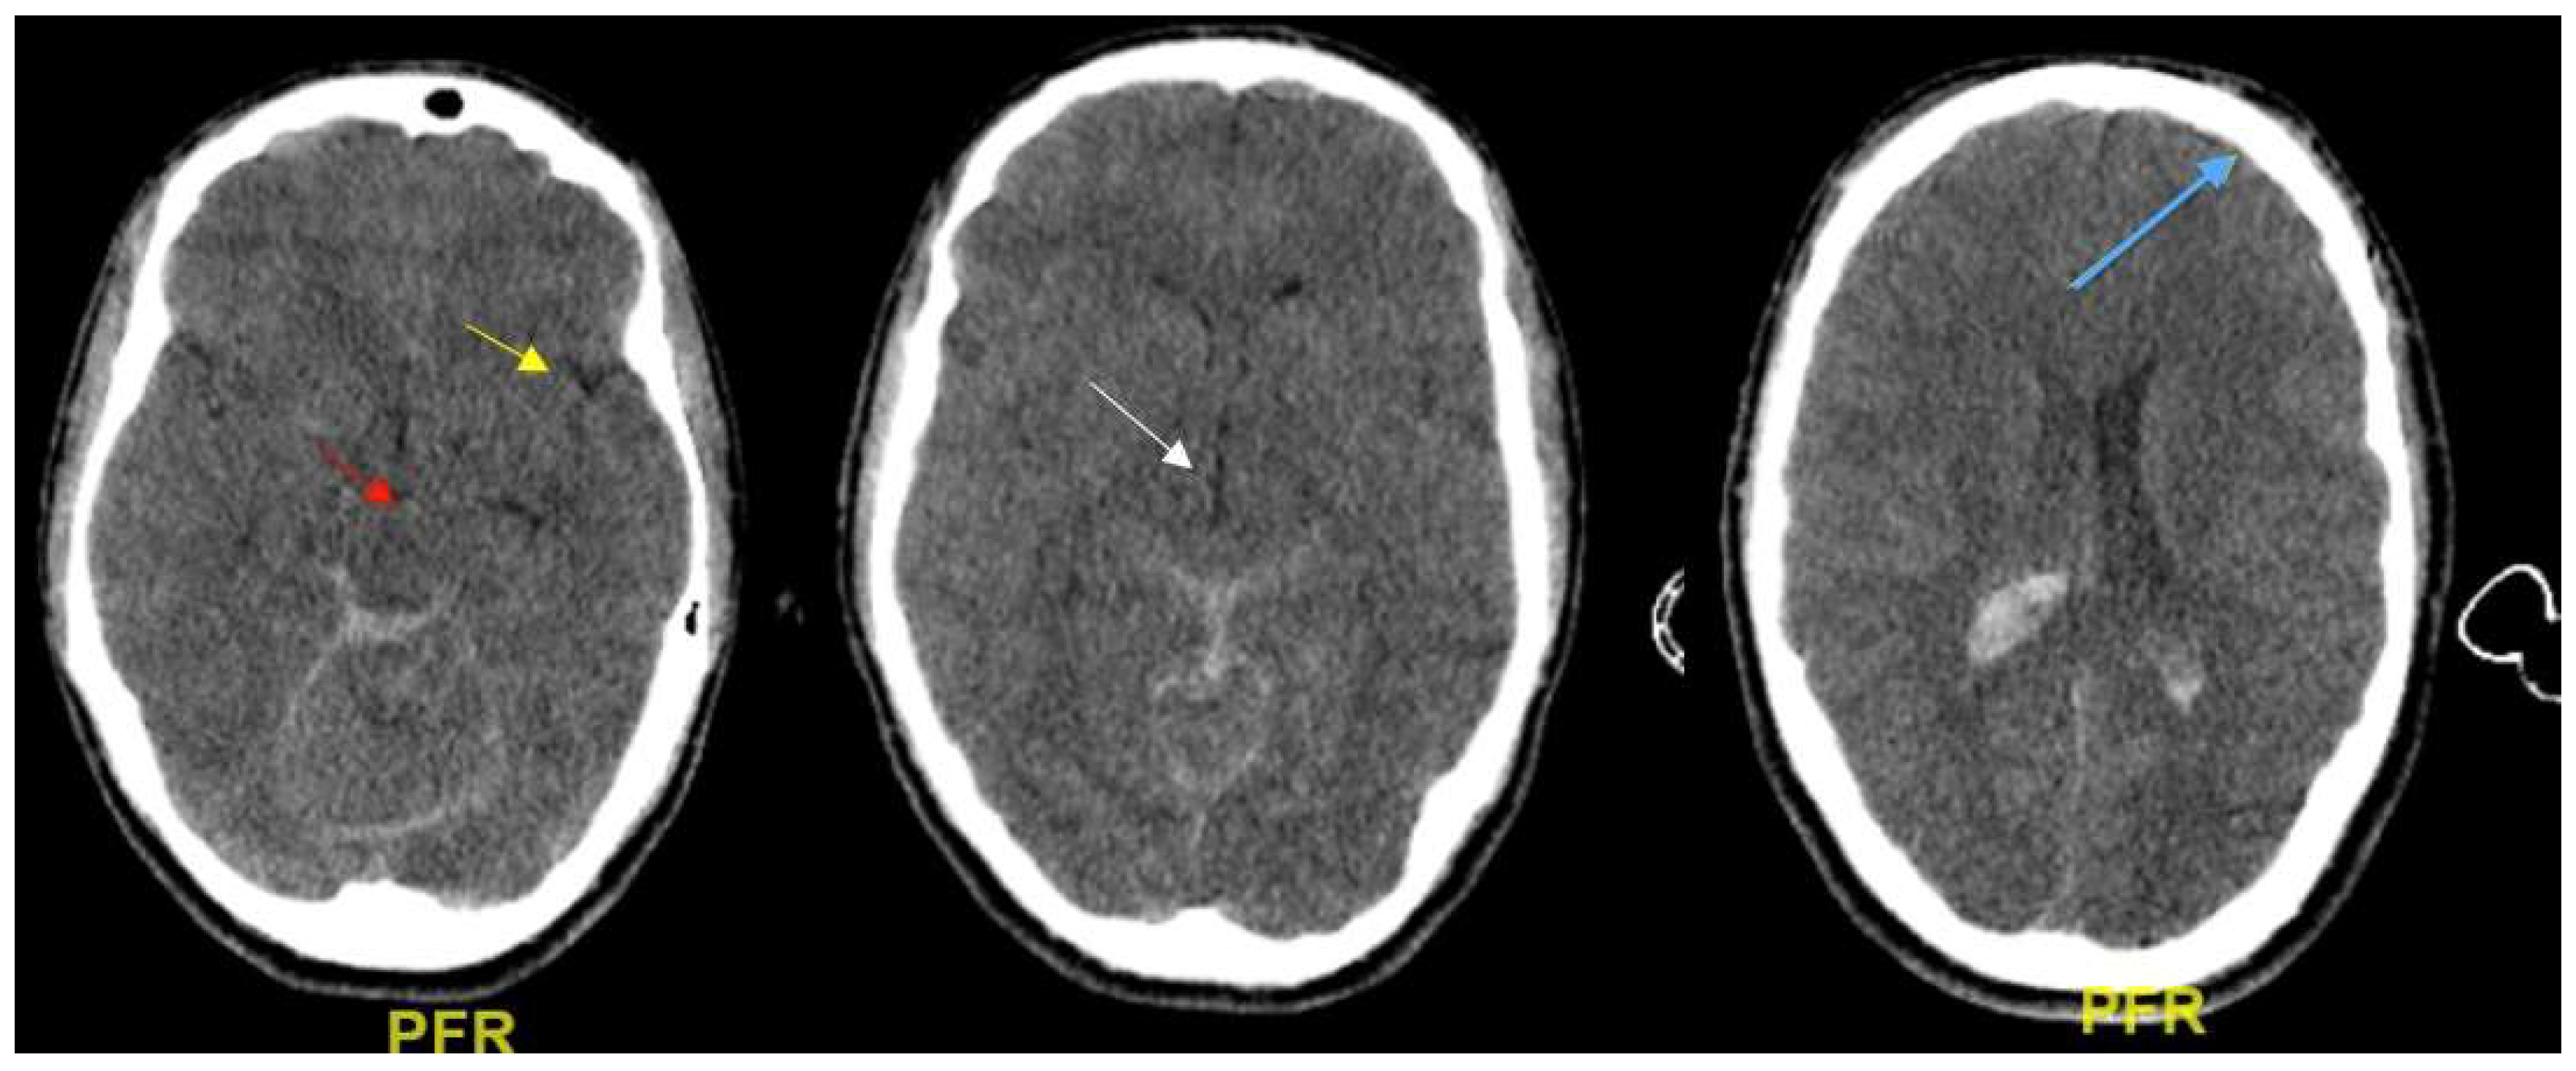

2.2. Evaluation of Brain Edema from CT Scans